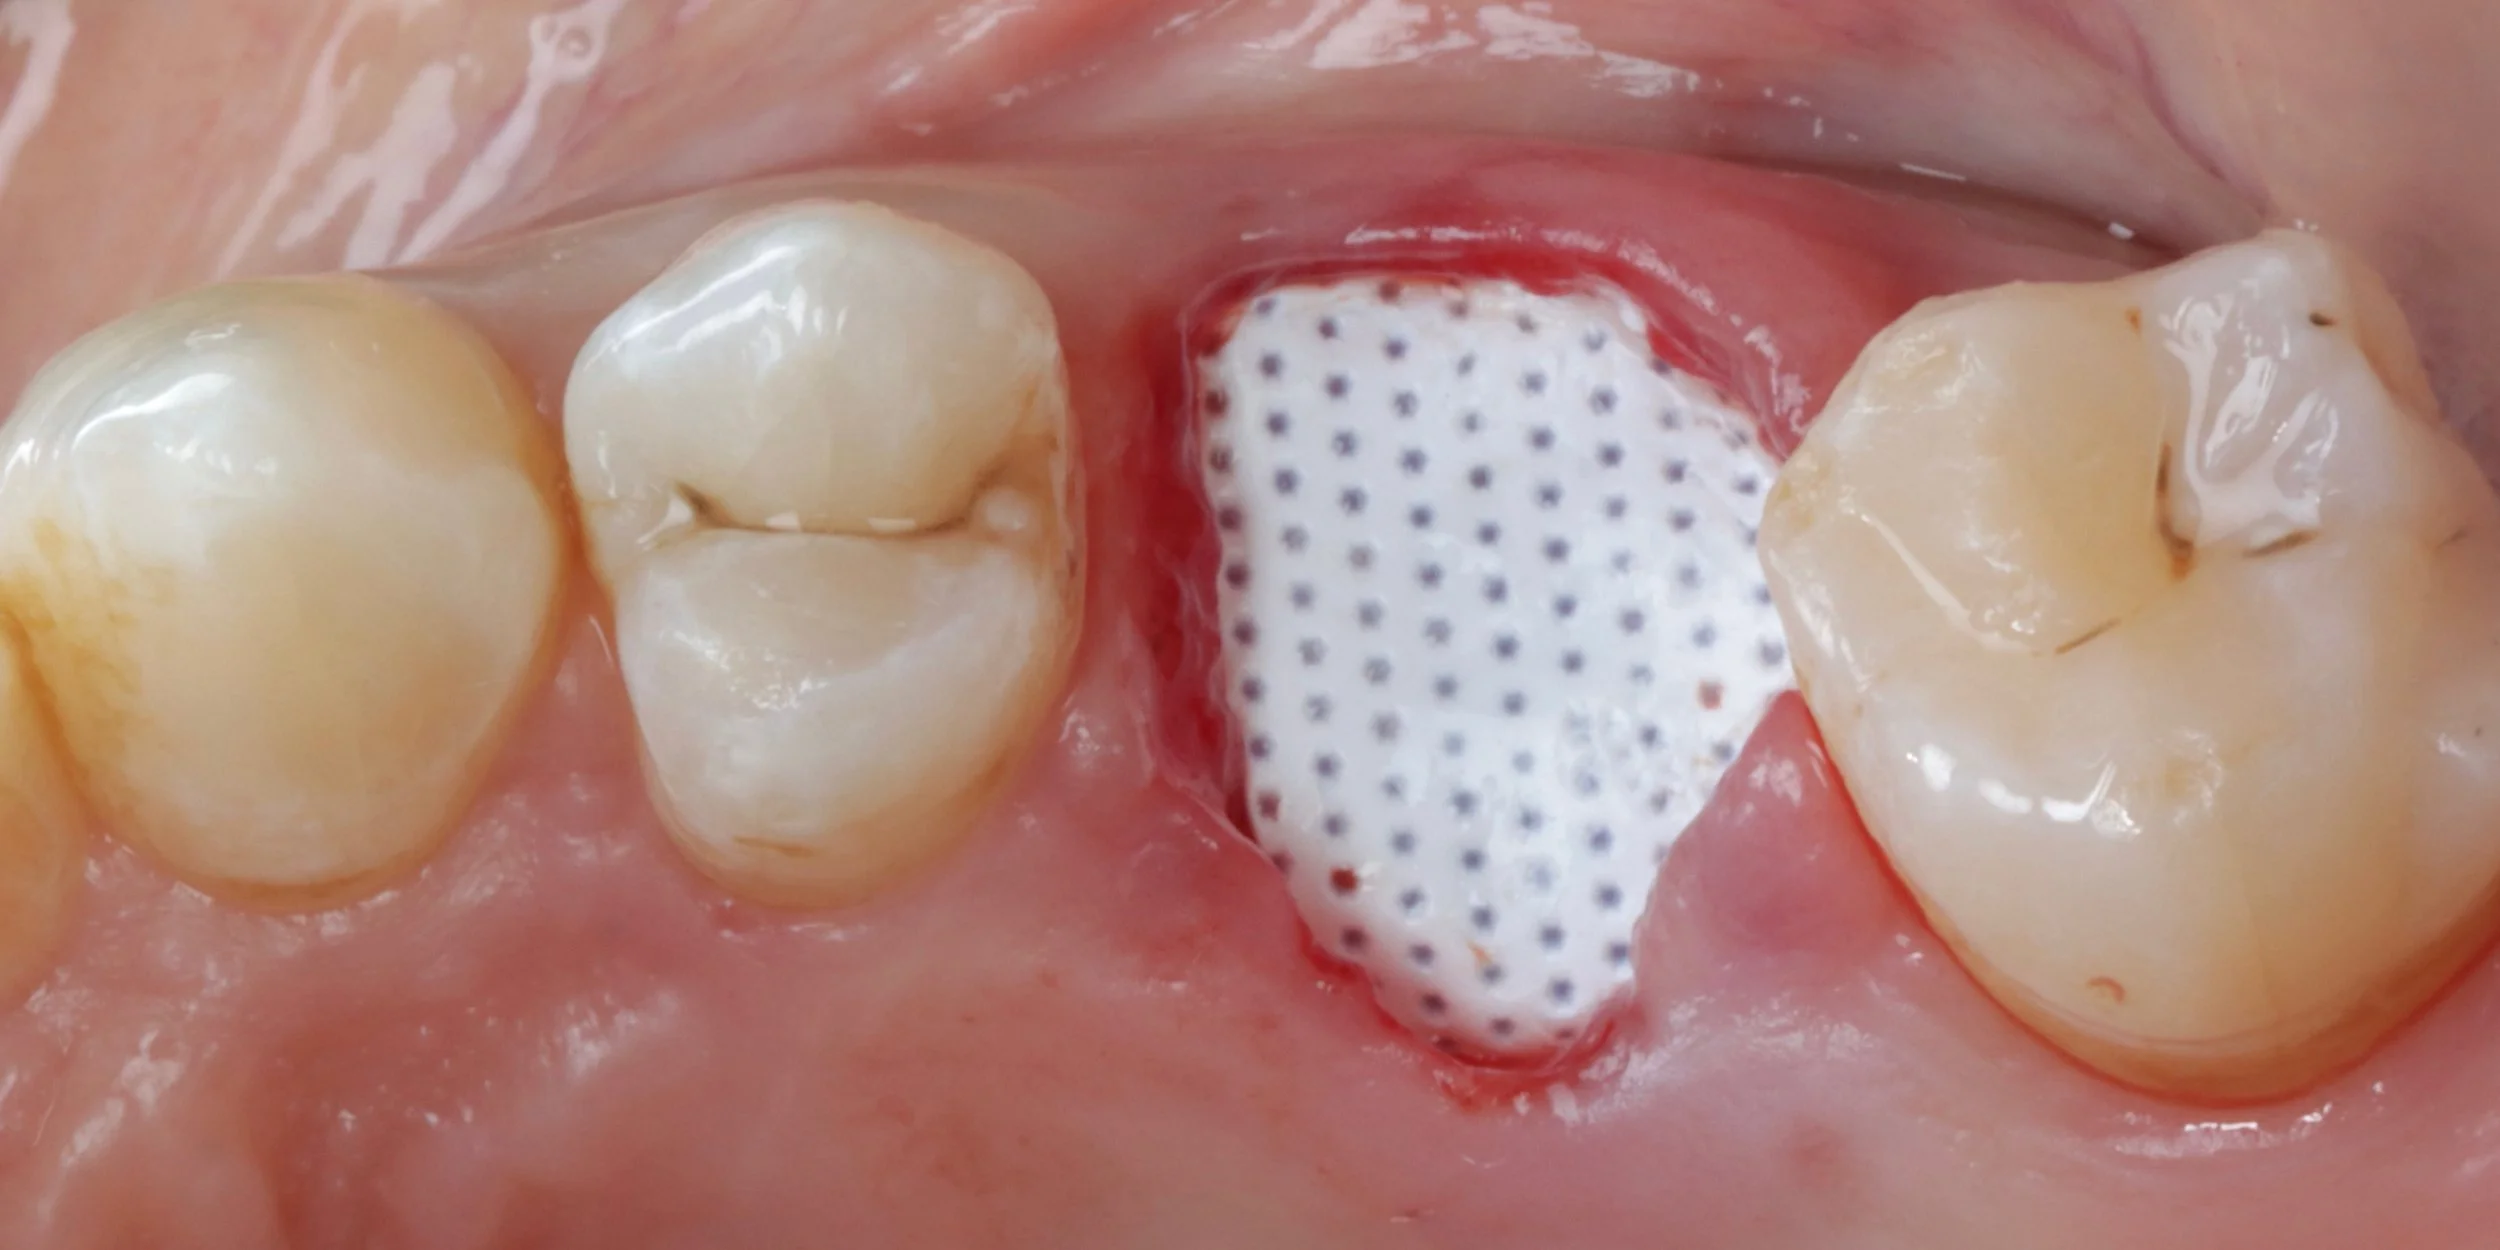

This under utilised yet highly valuable skill forms the foundations to help maintain gingival and alveolar architecture. From the general to the implant dentist, 15c will provide you with a predictable and simplified approach to ensure you can cultivate the ideal conditions for future implant or bridge placement for your patients. Learn surgical tips to improve your extraction and suturing techniques. Become confident in socket debridement and cleansing. Understand and see the different biomaterials available and the advantages and disadvantages of each. Practice how to use all of these skills to neatly and confidently perform socket preservation in practice.